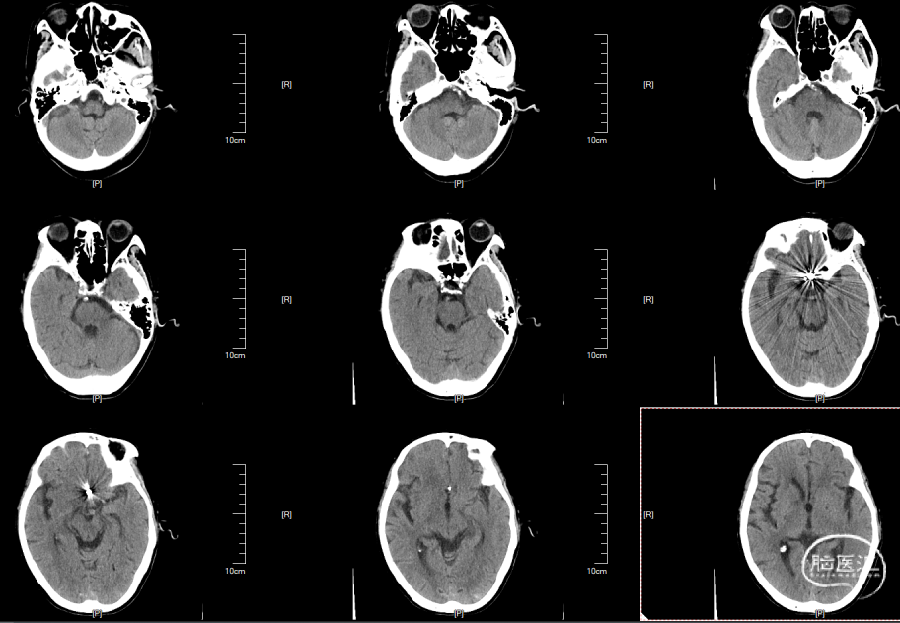

头颅CT见双侧外侧裂池、基底池、鞍上池高密度影,考虑蛛网膜下腔出血。

术后转神经重症监护,留置腰大池引流管,予抗感染、解痉、补液、护胃、控制颅压、预防癫痫等治疗。

术后24小时复查头颅CT:

03-21复查头颅CT:

术前头颅CT:

患者术后一般情况平稳,复查头颅CT未见出血,出院随诊。

24小时后复查头颅CT: